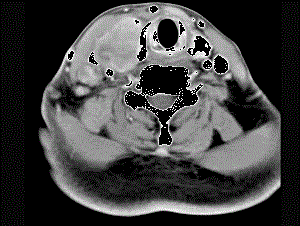

问题 女性,54岁,右侧颈部肿大近1年,近来病人有声嘶、吞咽困难,CT扫描如图,请选择正确的描述和答案 ( )

选项 A、考虑甲状腺癌 B、右侧颈内静脉瘤栓形成 C、增强扫描示甲状腺呈不规则强化团块影,其内有低密度区,病灶境界不清 D、右侧颈内静脉增粗,其内可见不规则充盈缺损区 E、右侧甲状腺肿大,密度减低

答案 ABCDE